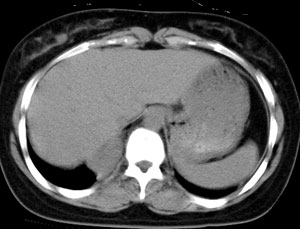

女,22岁,无明显症状

强化

首先定位在肺内。肿块最大径在右下肺叶后基底段,胸椎椎体右边偏后部。与气管、食管无关,如果是支气管或食管囊肿应该有细蒂与之连接。肿块边缘光整、密度均匀一致、轻度均匀强化。右主支气管轻度受压,右肺含气量降低,右胸腔略萎陷。

手术证实 支气管囊肿

自己分析一下误诊的原因,如果不对,请老师们指正:该肿瘤位于支气管分叉处,附着于右主支气管后外壁。因为病灶逐渐长大和重力的关系,呈水滴状下垂,故造成其最大径不在纵隔内的假象。轻度强化也是没有仔细和平扫对比给自己造成的假象。才疏学浅,没有仔细分析病例,也没有仔细体会各位老师的不同意见,草率之至,羞愧!